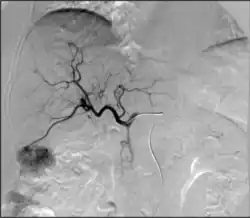

• Эмболизация воротной вены (ЭВВ): доставка эмболического материала в воротную вену, питающую долю печени, содержащую опухоль(и), представляющую интерес, для стимуляции роста здоровой доли для поддержания адекватной функции печени, необходимой для проведения хирургической резекции доли, содержащей опухоль(и).[37]